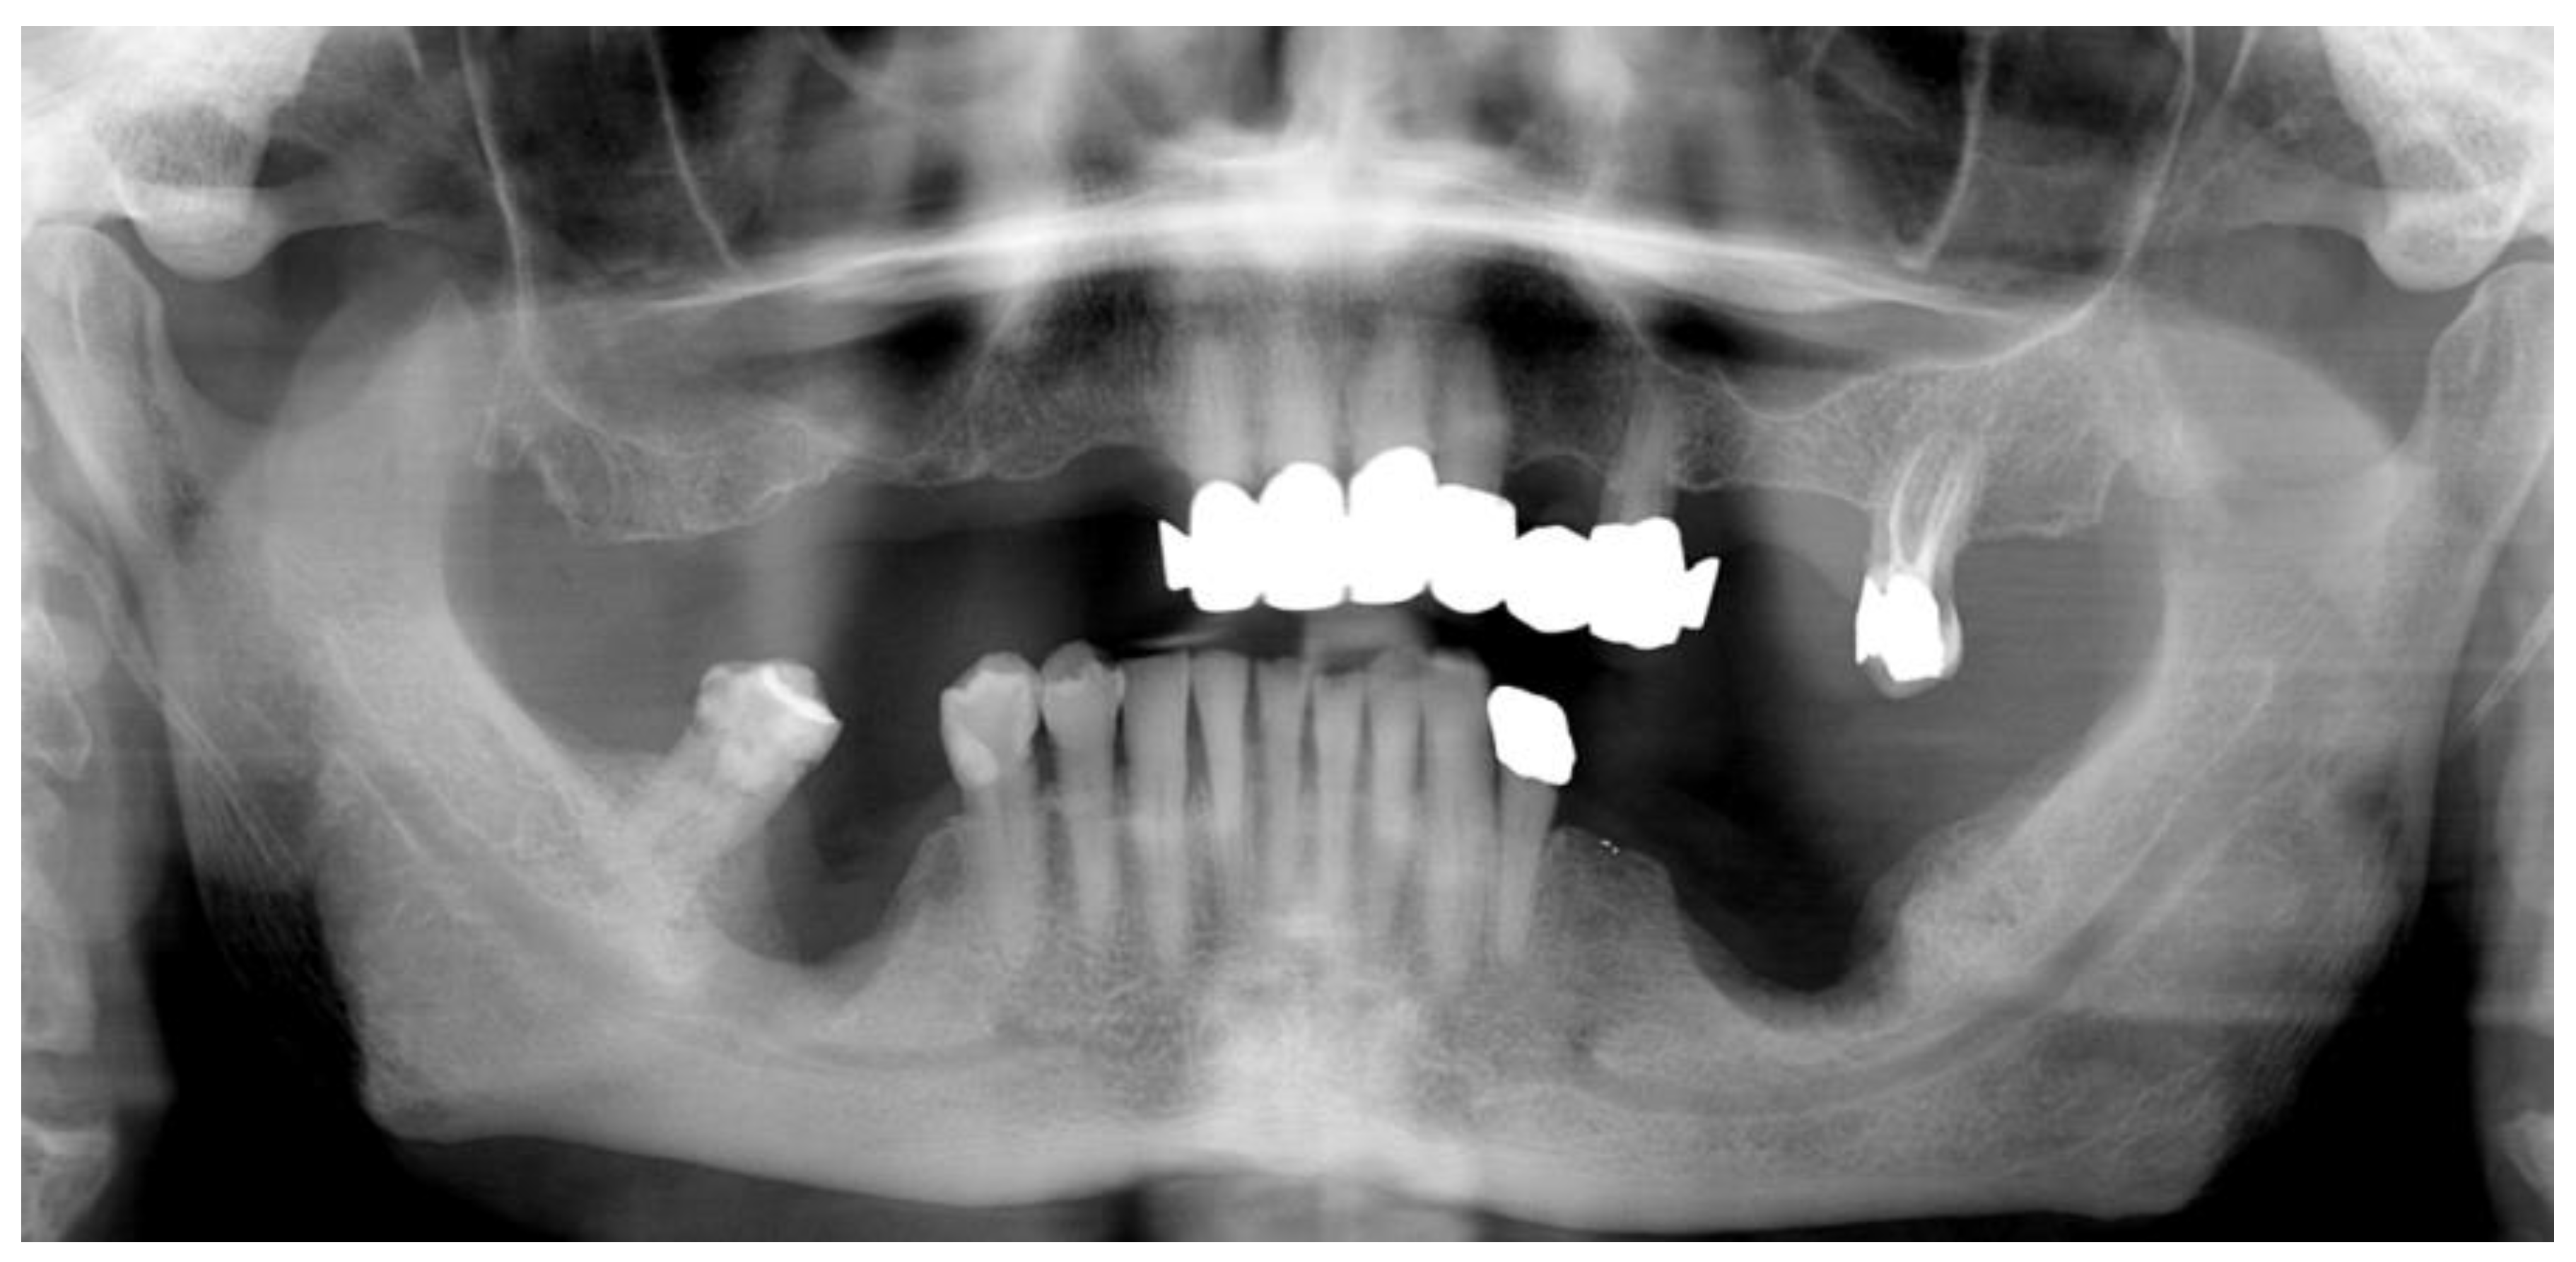

2.1. Case Presentation

- Pre-operative evaluation. The patient undergoes a cone-beam CT exam with a reference plate containing the fiducial markers, fixed on his inferior teeth. The Digital Imaging and Communications in Medicine (DICOM) were imported into the navigation software.

- Surgery timing. The surgeon can follow in real time the ultrasonic tip position onto the system screen displaying the CBCT images and safely identify and remove the necrotic bone surrounding the inferior alveolar nerve on the right side.